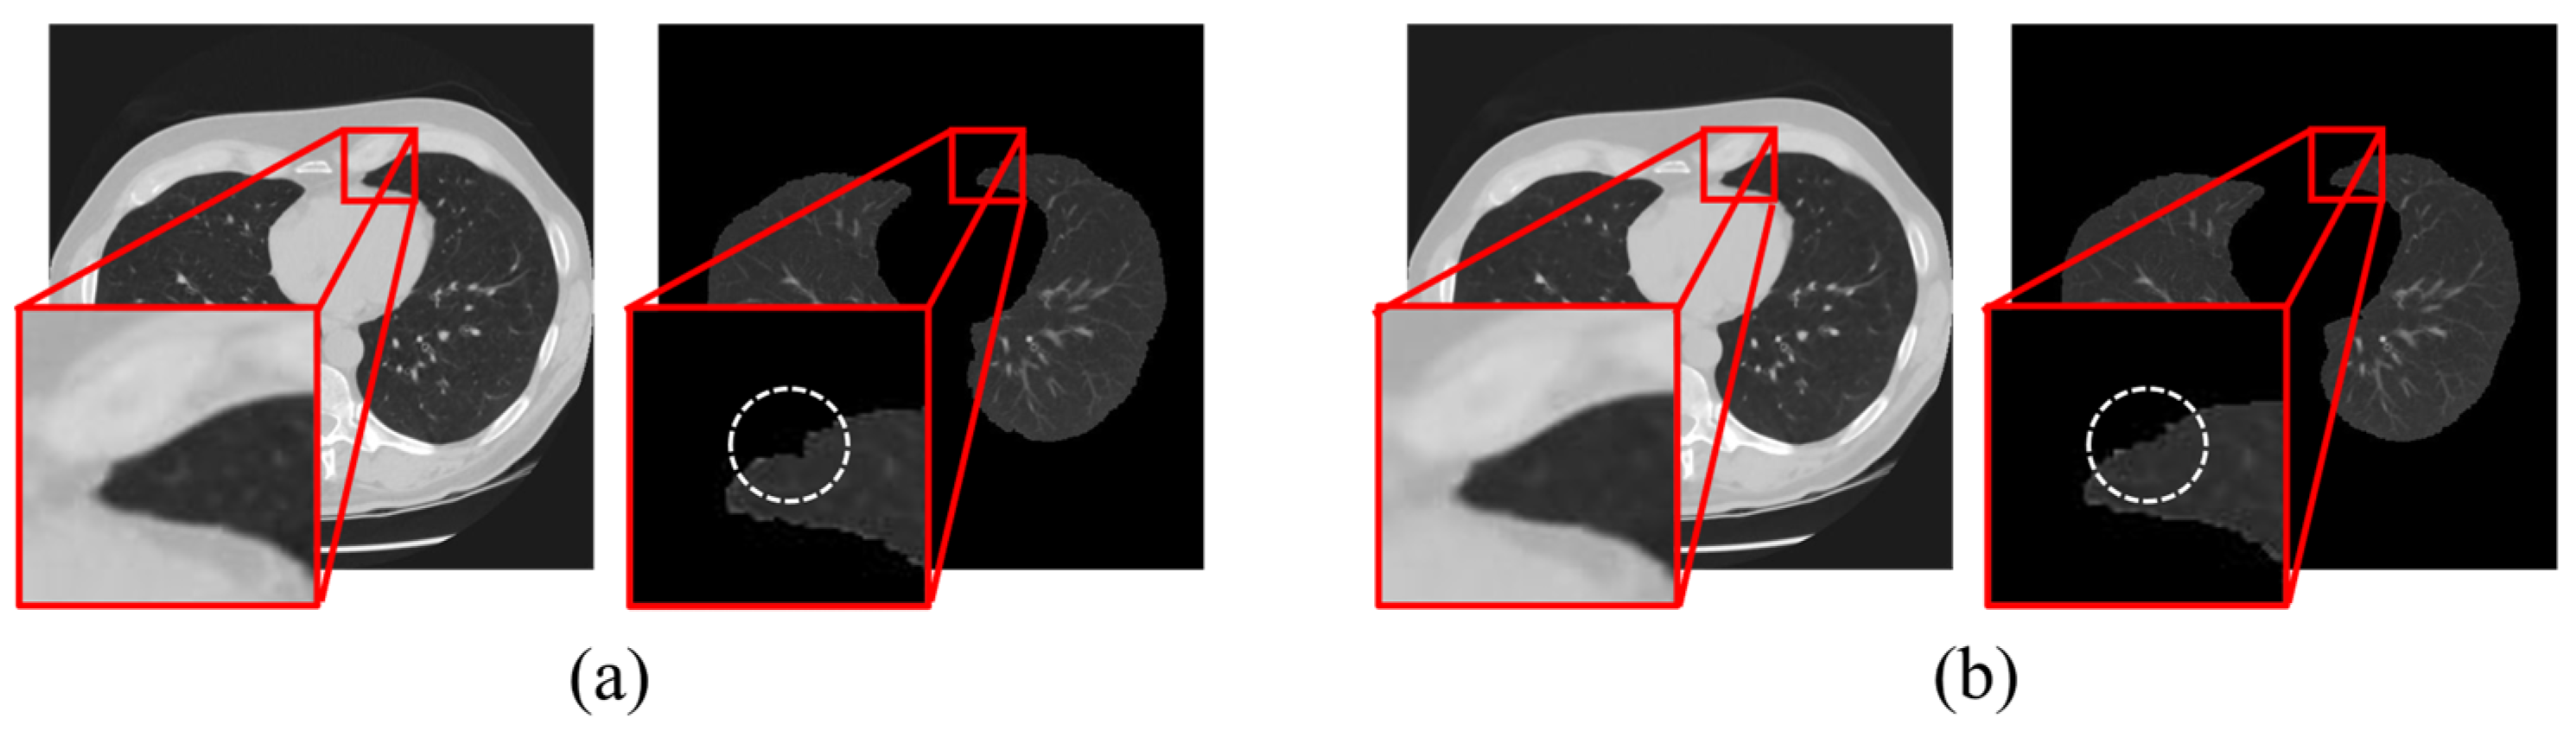

We observed that when the kernel size was too small, the noise removal was inadequate, leading to uneven lumen signals and a degradation in segmentation performance (Figure 6). Setting a high threshold value to overcome this problem can result in excessive tissue segmentation. Conversely, when the kernel size is too large, edge information is lost, making it difficult to distinguish the Hounsfield unit differences between tissues. Lowering the threshold value to address this problem resulted in improper tissue segmentation.

Figure 6.

Illustration of region-growing performance for lung segmentation using MMWF-based denoising with (a) 3 × 3 and (b) optimized kernel size 5 × 5.